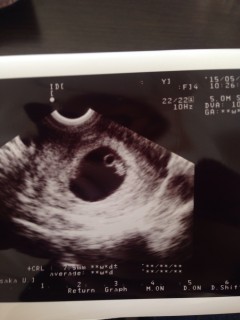

予定日は来年の7月29日現在7週2日です! 大きさでは6週6日の大きさで8.1mm 心拍も確認でき小さな心臓がピコピコ動いてました! 2歳の息子も一緒にいって かーいねー。と(^^♪ ですがいま切迫流産気味で自宅安静に… 次の二週間後の検診9週目… げんきでありますように…(/_;) 子供を信じて大人しくしてようと思います!